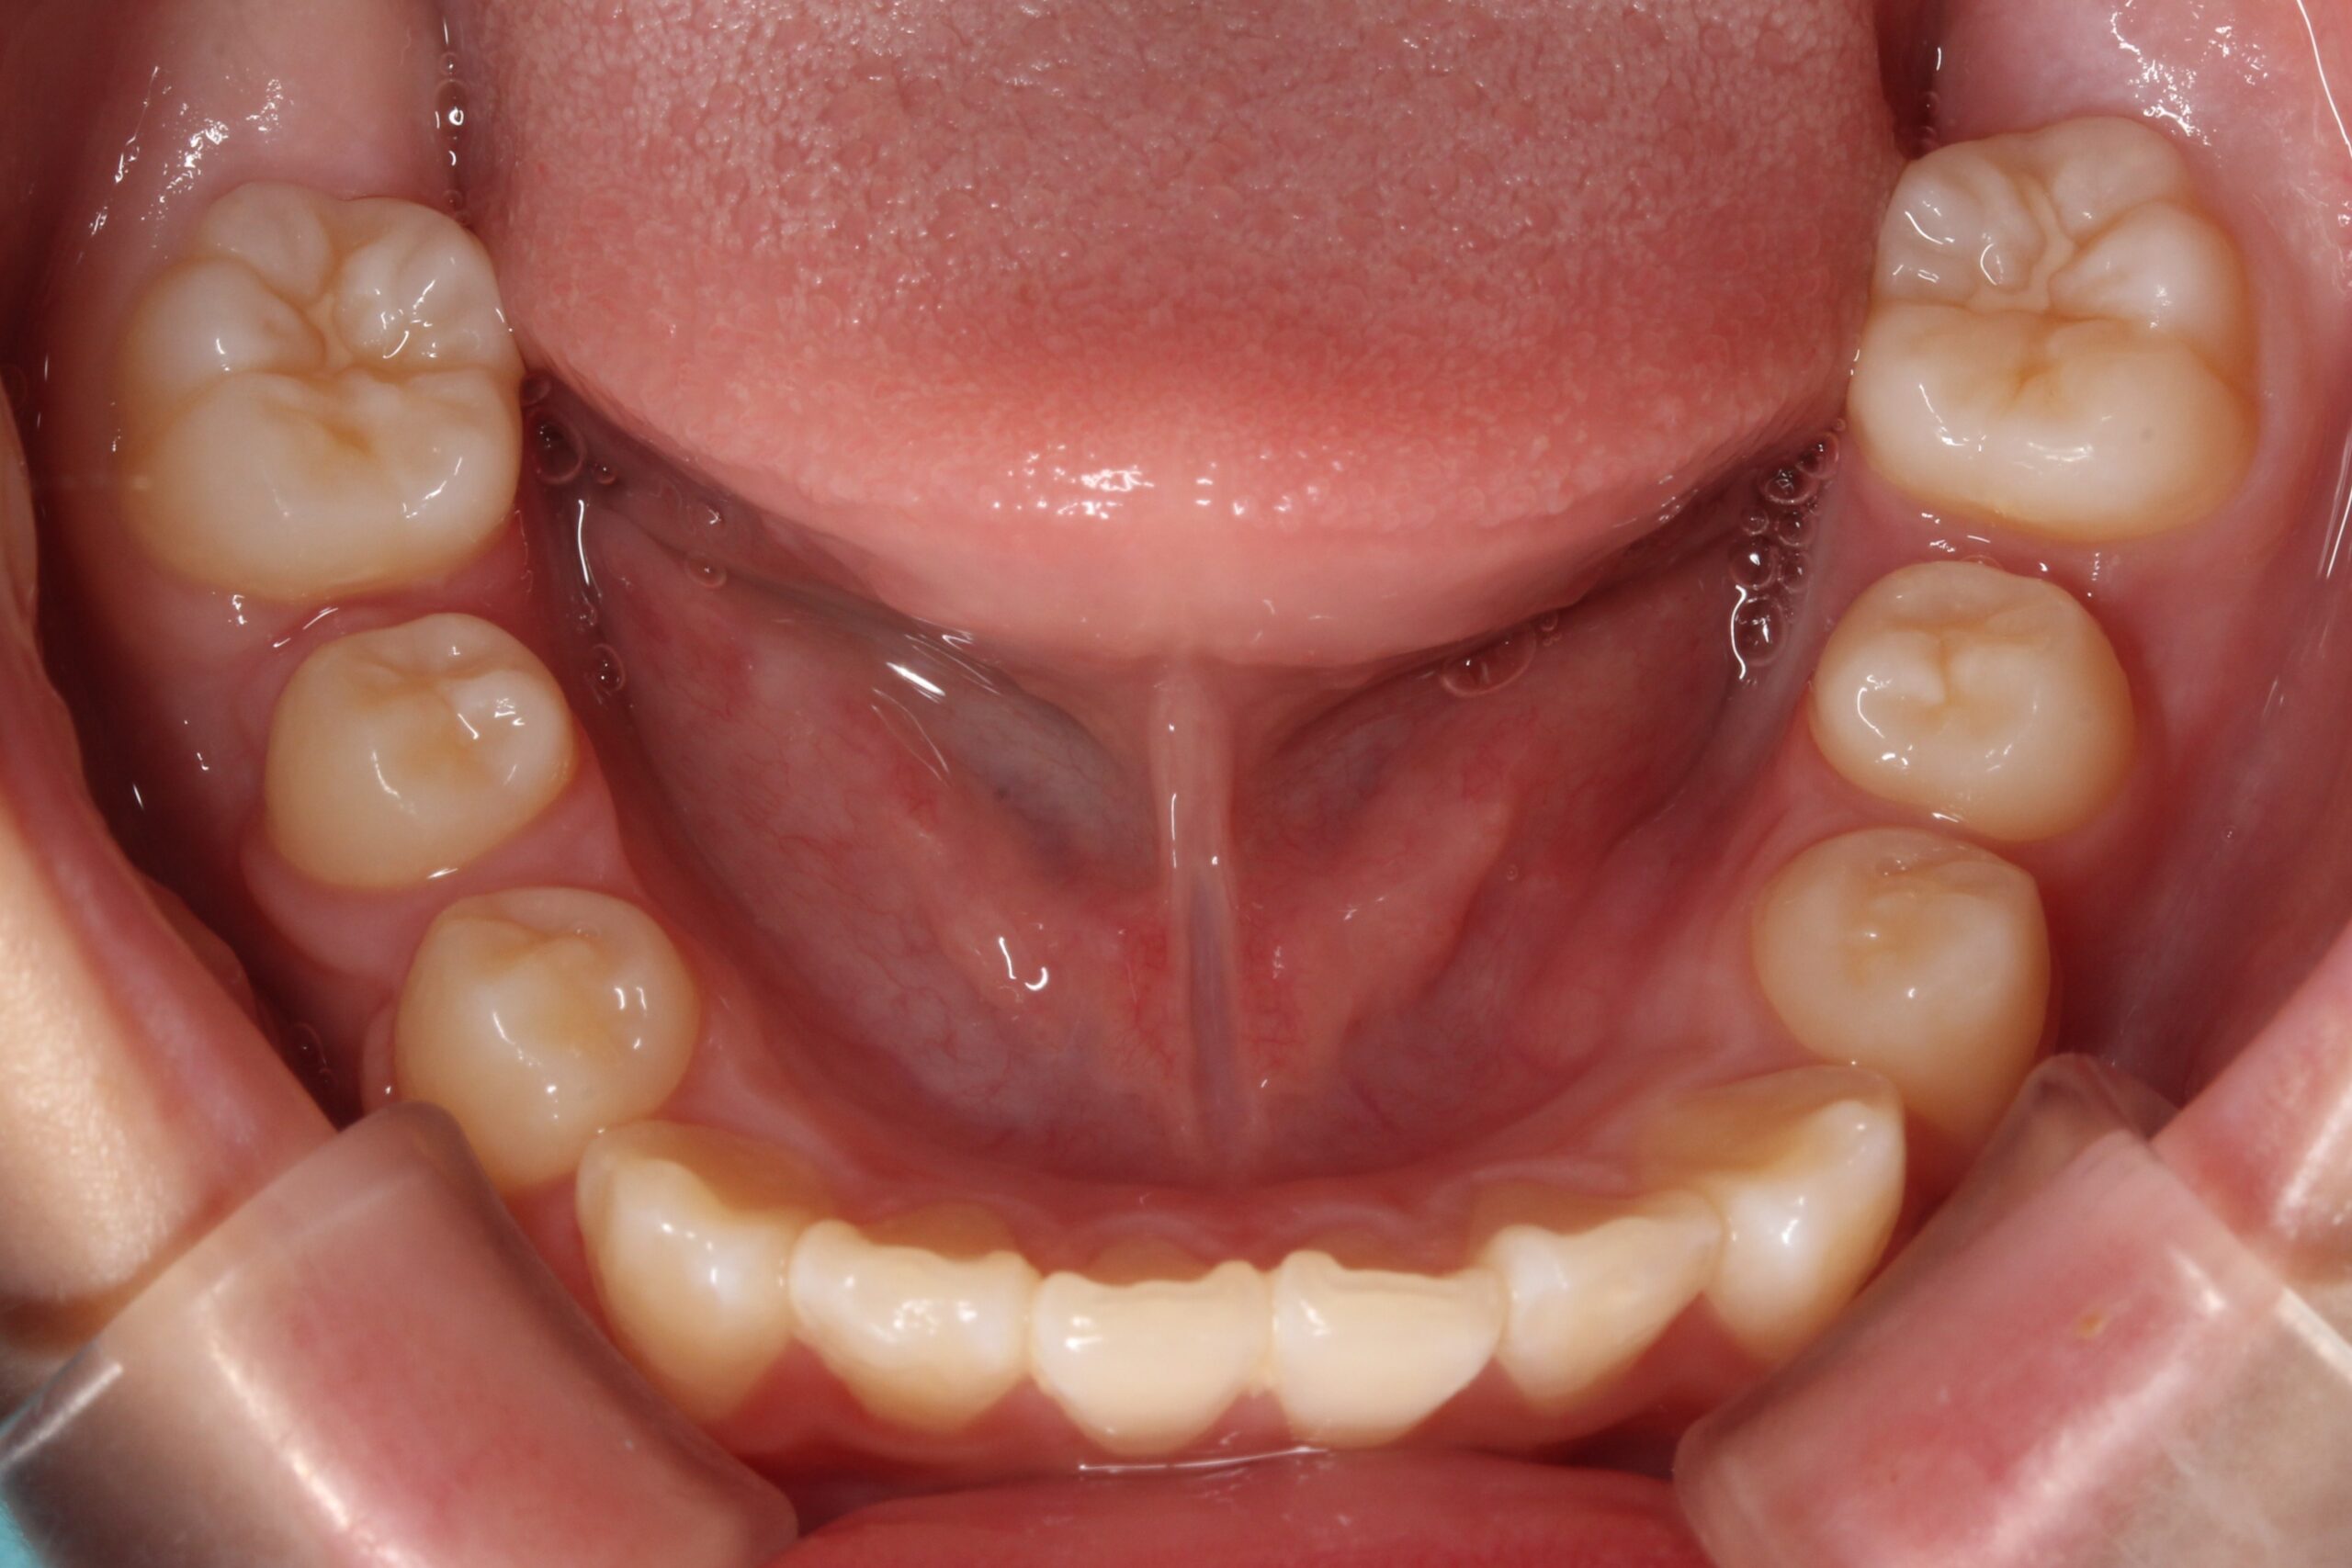

矯正術前:下顎

矯正術後:下顎